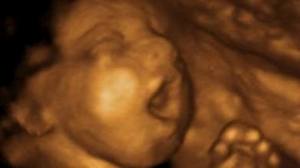

baby